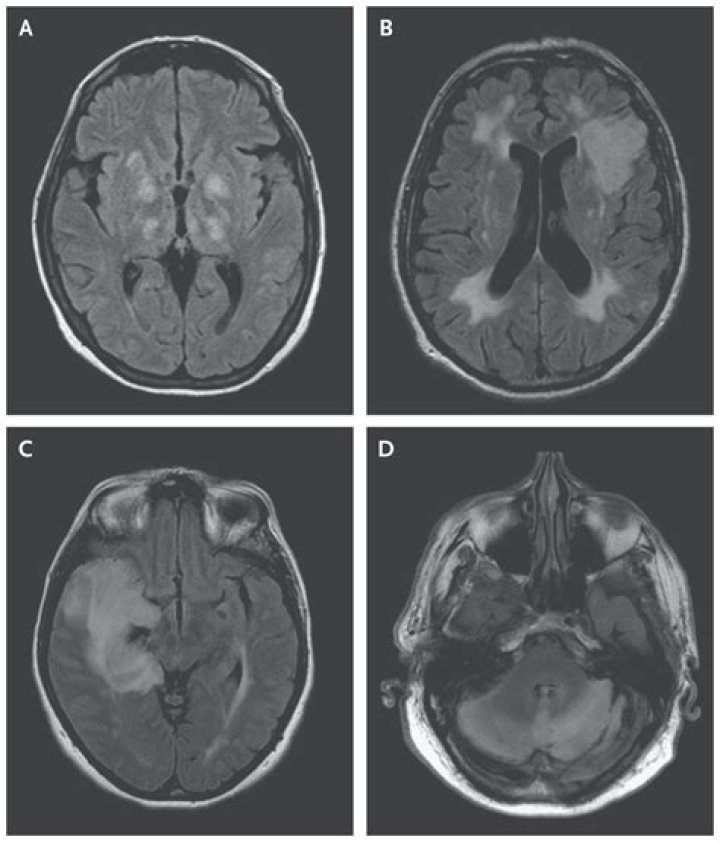

Imaging CNS autoimmune and inflammatory disease - 2 - Encephalitis

Sarah Smith Laboratory investigations, imaging, and cerebrospinal fluid analysis are crucial in the diagnosis of encephalitis. Magnetic resonance imaging (MRI) findings may be nonspecific or specific and plays a major role in the diagnosis of encephalitis and predicting the possible cause.

What does encephalitis look like on CT?

The brain MRI is normal in approximately 60% of patients with anti-NMDAR encephalitis. Very few studies have systematically investigated neuroimaging in all-cause encephalitis. Research is needed to better define associations between neuroimaging results and specific encephalitis aetiologies.